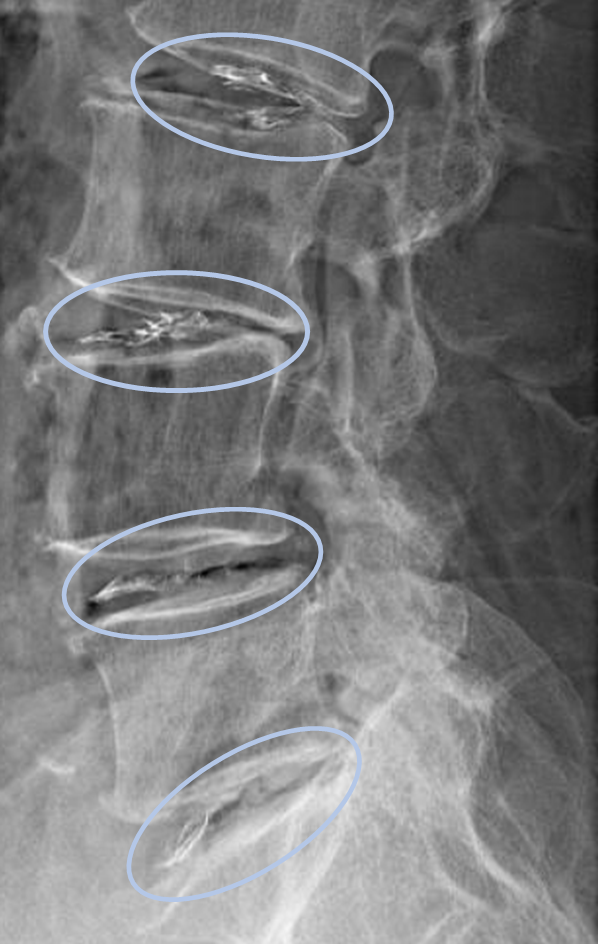

画像及び所見について

• L2/3,3/4,4/5,5/s-椎間板変性

• L2/3-椎間板ヘルニア

以上の事が画像上認められます。

・L3/4,4/5,5/s-椎間板変性を認め、予防的側面から

・L2/3-椎間板ヘルニアを認め、主症状の原因の可能性が高い

DiscoGelを入れた後の画像になります。